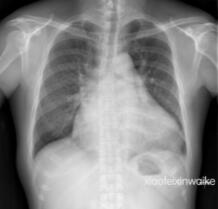

这是一名男性患者,49岁,因反复劳力性呼吸困难14年,加重伴双下肢浮肿1月余入院。心脏超声发现这是一颗早就不堪重负的心脏:风湿性心脏病,联合瓣膜病,主动脉瓣重度狭窄,收缩峰值压差高达94mmHg;二尖瓣重度狭窄,瓣口面积仅为正常人的1/4;三尖瓣返流面积达到了惊人的19.3 cm2;肺动脉收缩压高达119mmHg,更是正常上限的4倍。心胸比例为0.71(图1)。

患者术前的胸片